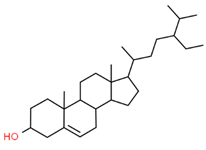

| 17 |  | 222284 | C29H50O | 414.7 | CCC(CCC(C)C1CCC2C1(CCC3C2CC=C4C3(CCC(C4)O)C)C)C(C)C |  |